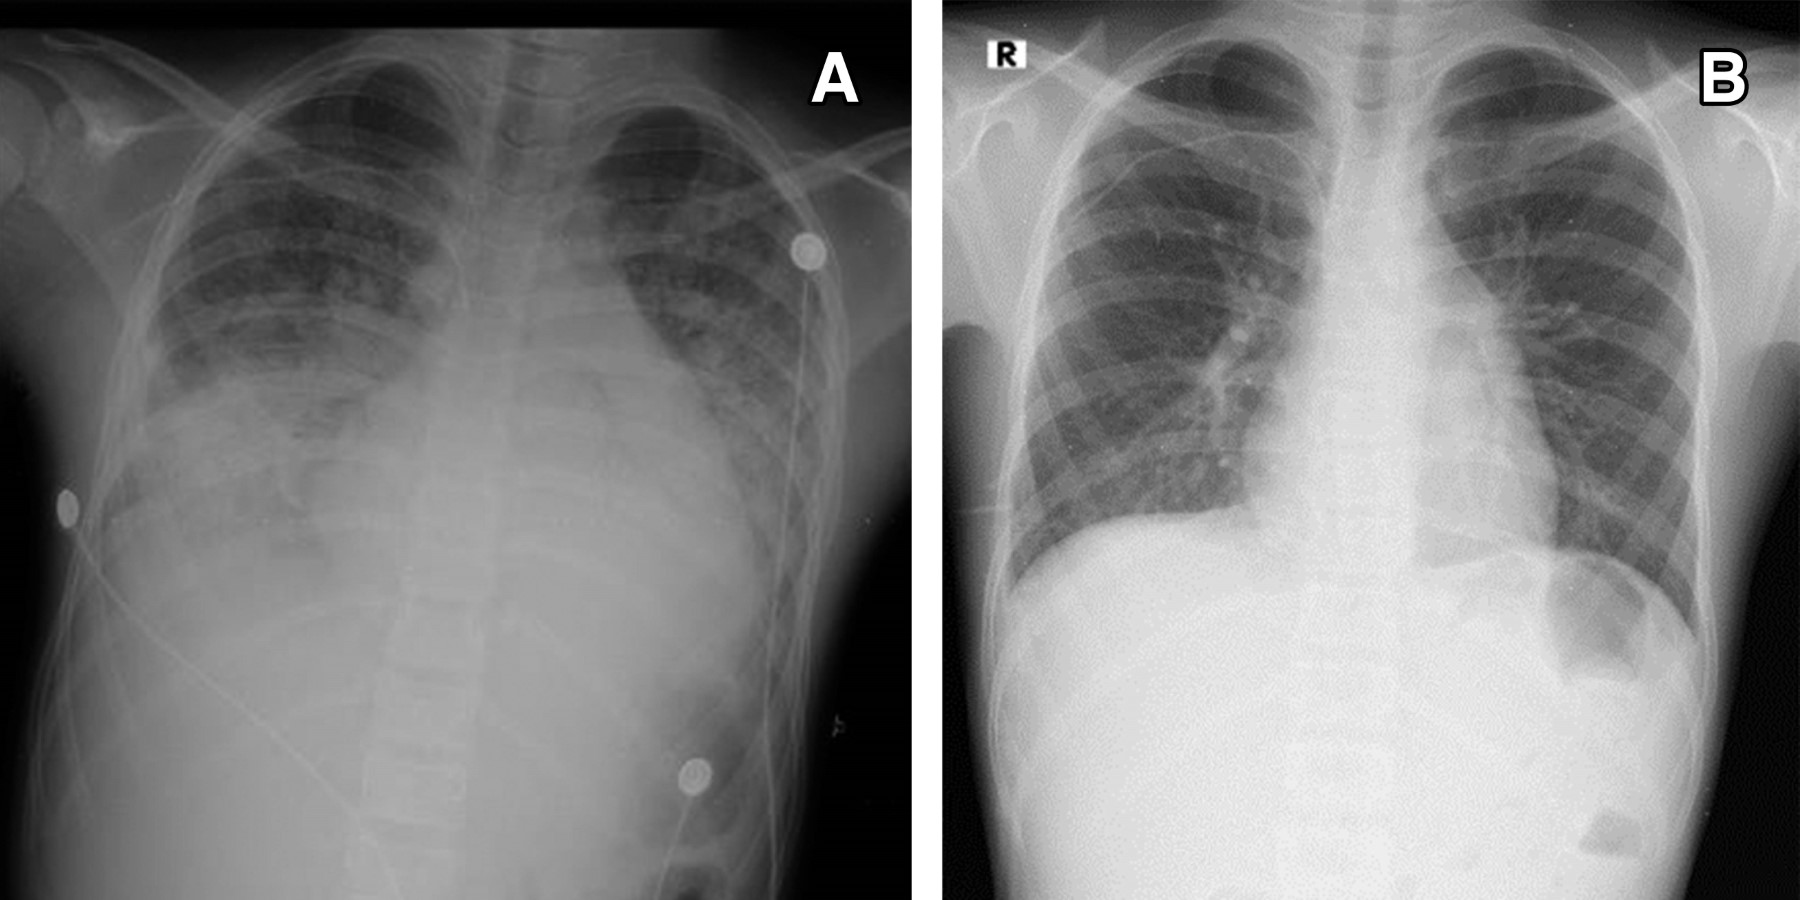

Figure 2